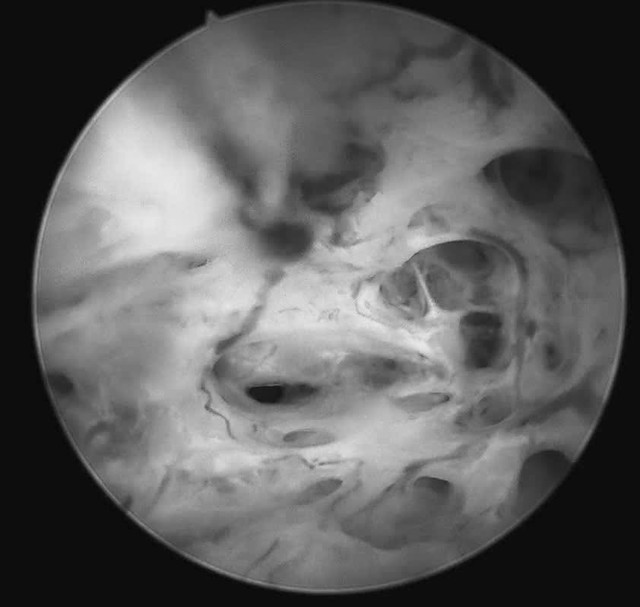

Trước tình huống đó, tại Khoa Khám phụ khoa tự nguyện, bệnh nhân được tư vấn thực hiện soi buồng tử cung sinh thiết bằng ống soi nhỏ, một phương pháp cho phép đánh giá trực tiếp buồng tử cung mà không làm tổn thương màng trinh. Ca thủ thuật được ThS.BSCKII Nguyễn Biên Thùy - Trưởng khoa Khám Phụ khoa Tự nguyện trực tiếp thực hiện.

Quá trình soi diễn ra an toàn, nhẹ nhàng. Bệnh nhân hoàn toàn tỉnh táo và có thể quan sát trực tiếp hình ảnh buồng tử cung. Mẫu sinh thiết được lấy ngay trong quá trình soi để làm xét nghiệm mô bệnh học. Kết quả xét nghiệm cho thấy bệnh nhân bị ung thư niêm mạc tử cung.